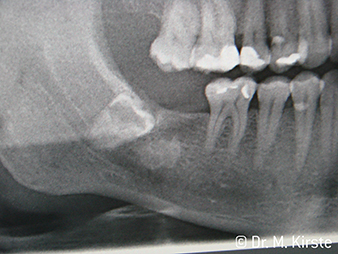

Per la prima volta, gli strumenti di trasmissione WS-91 e WS-91 L G combinano i vantaggi dei manipoli e dei contrangolo chirurgici (figura 1). Sul lato anteriore, l'angolo ampliato tra l'area di presa e l'asse di foratura consente un accesso ottimale alla zona buccale e occlusale, sopra la fila di denti (figura 4). I denti malposizionati possono essere separati con semplicità (figure 6 e 7). Inoltre, la visuale della persona addetta al trattamento sull'area di intervento è notevolmente migliore rispetto agli strumenti disponibili in passato. Ecco l'opinione del dott. Mario Kirste di Francoforte sull'Oder: "Quando ruoto leggermente la testina del contrangolo, posso lavorare in modo particolarmente sicuro e rapido nell'area retromolare. Lo strumento ha il potenziale per conciliare gli schieramenti contrapposti di chi usa i contrangolo e chi usa i manipoli.“ (figure 2 - 5)

Un ulteriore campo di utilizzo dei contrangolo WS-91 e WS-91 L G è la resezione di apici radicolari. Anche con i molari dell'arcata superiore e quando l'apertura orale è ridotta, l'ergonomia dello strumento consente un'ottima visuale. Con il WS-91 L G viene fornito anche un Mini-LED+, che illumina a giorno l'area di trattamento. Il Dott. Kirste afferma: "I nuovi contrangolo rappresentano una transizione davvero riuscita. La straordinaria efficienza tecnica degli strumenti W&H amplia le mie vedute e le mie possibilità negli interventi di chirurgia quotidiani."